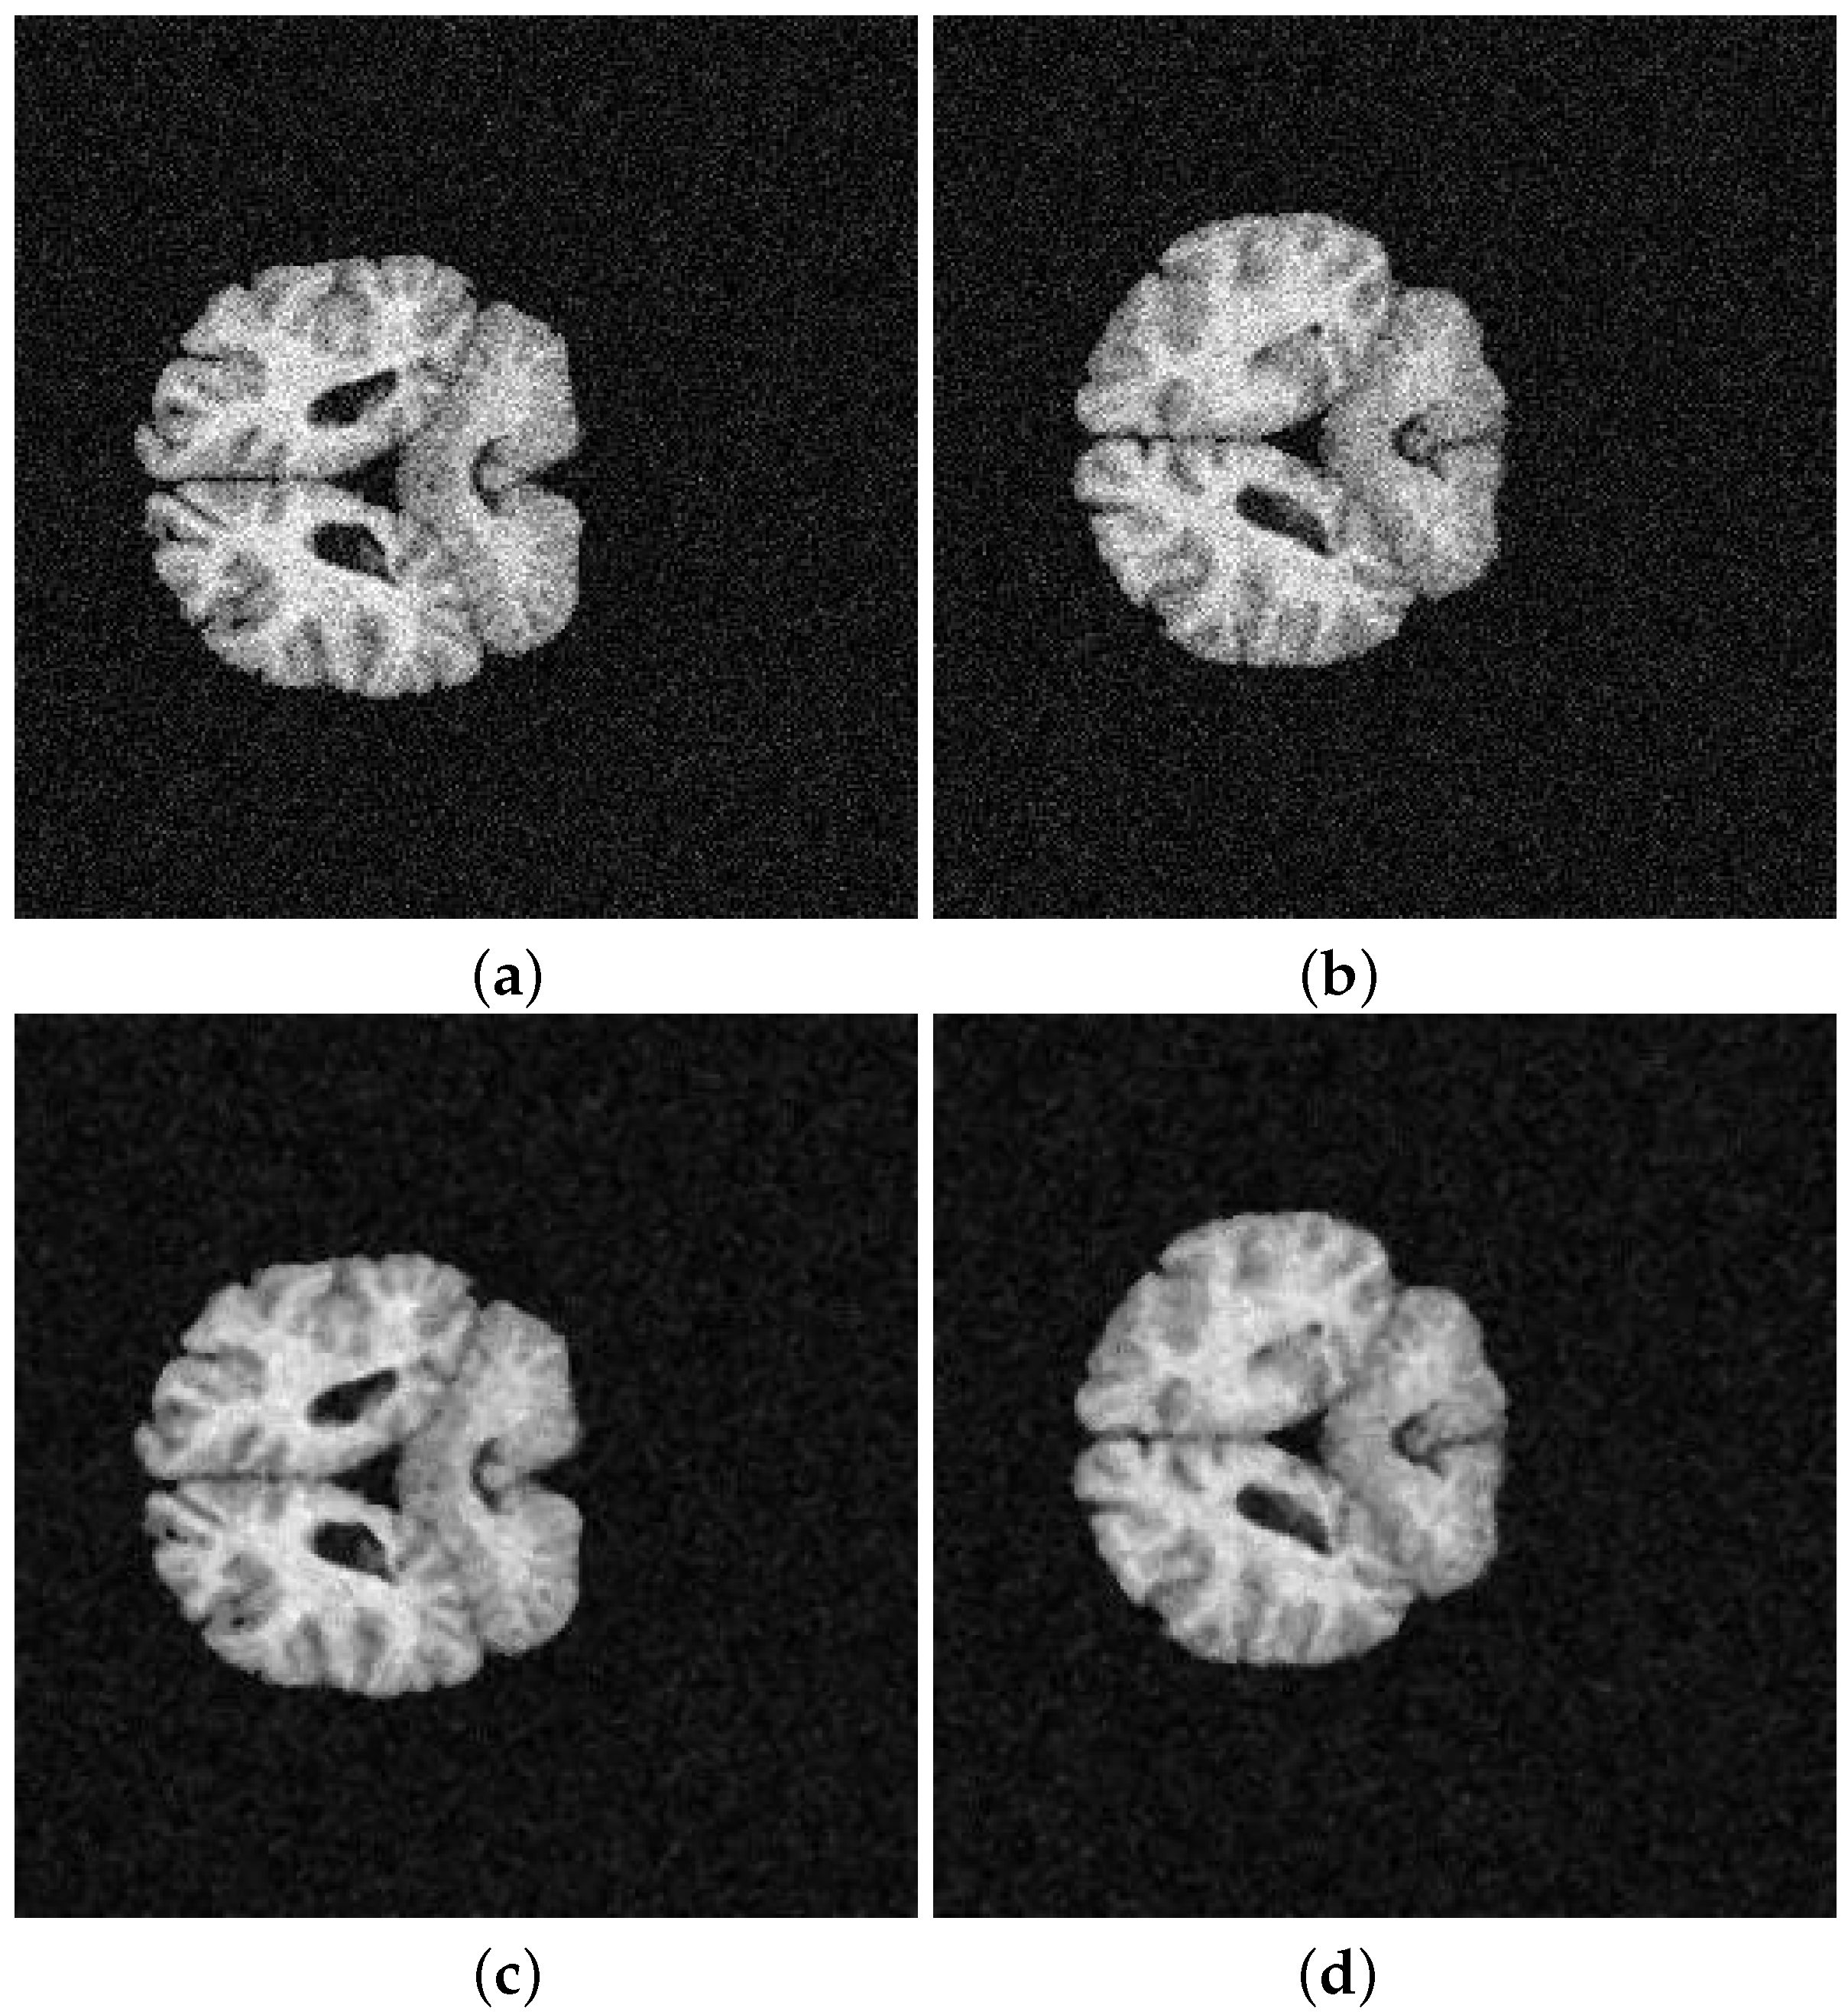

| Segmented Image | K-means | FCM | SFCM | KFCM |

|---|---|---|---|---|

| 202-3 original | 0.5842 | 0.5850 | 0.5832 | 0.5889 |

| 202-3 with noise | 0.5859 | 0.5873 | 0.5856 | 0.5845 |

| 205-3 original | 0.5793 | 0.5781 | 0.5758 | 0.5761 |

| 205-3 with noise | 0.5763 | 0.5787 | 0.5761 | 0.5782 |